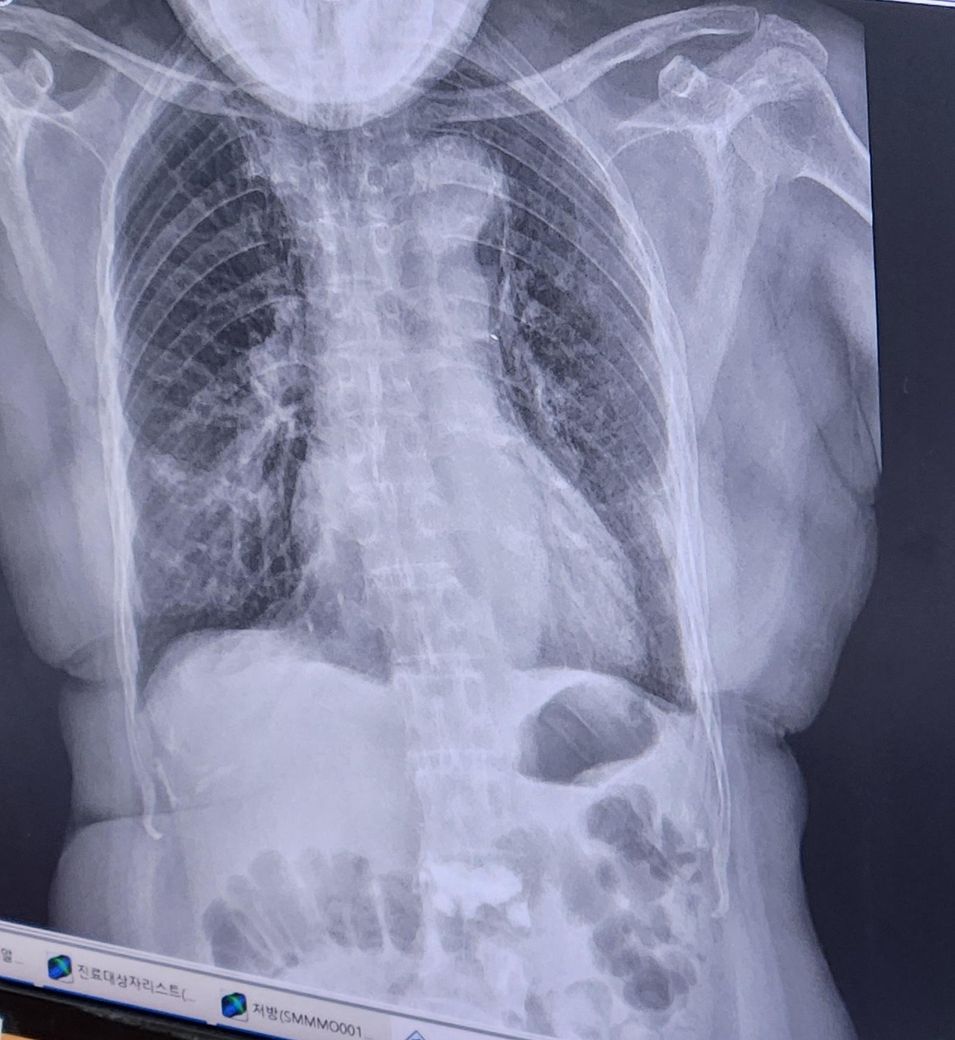

각각 다른 병원에서 찍은 엑스레이 사진인데

위에꺼가 일주일전 아래가 일주일후입니다.

일주일전 사진에는 뭉쳐져있는것들이 있는데

아래는 풀어져서 퍼진것처럼 보여서요.

다른 병원에서 찍어서. 비교가안되어 여쭤봅니다

위에사진의 뭉덩이진것이 아래사진에서 풀어진것이라면. 호전되고있는건지 궁금합니다

• 1번 째 사진

딱히 호전되었다고는 보이지 않습니다.

폐렴의 정확한 상태는 단순히 엑스레이로는 판단 불가합니다

임상적 맥락을 모두 봐야 하기 때문에 혈액검사 결과는 물론 증상의 호전도까지 모두 총체적으로 평가해야 가능합니다

담당 의사와 상의 하셔야 정확해요

• 사진의 질이 달라서 판단하기 다소 애매한 부분이긴 하겠습니다만, 위의 사진이 초기의 사진이고 아래쪽 사진이 이후에 찍은 사진이라면 폐렴이 더 심해졌다고 볼 수 있겠습니다. 범위가 더 넓어졌고 뿌옇게 변한 부분이 더 많아졌습니다. 호전이 되고 있는 사진이라고 보기는 어렵습니다.